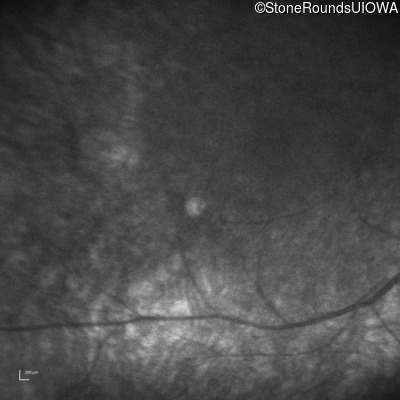

Infrared Fundus Photograph - Right -

No Light Perception

Exemplar

Expanded OCT Stack

×